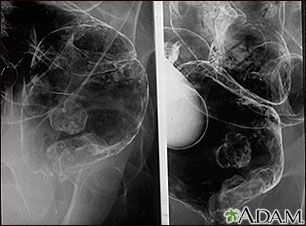

A barium enema is a special x-ray of the large intestine, which includes the colon and rectum.

- You then lie on your side. The x-ray technologist or radiologist gently inserts a well-lubricated tube (enema tube) into your rectum. The tube is connected to a bag that holds a liquid containing barium sulfate. This is a contrast material that highlights specific areas in the colon, creating a clear image.

- The barium flows into your colon. X-rays are taken. A small balloon at the tip of the enema tube may be inflated to help keep the barium inside your colon. The x-ray technologist or radiologist monitors the flow of the barium on an x-ray screen.

- Sometimes a small amount of air is delivered into the colon to expand it. This allows for even clearer images. This test is called a double contrast barium enema.

Barium should fill the colon evenly, showing normal bowel shape and position and no blockages.